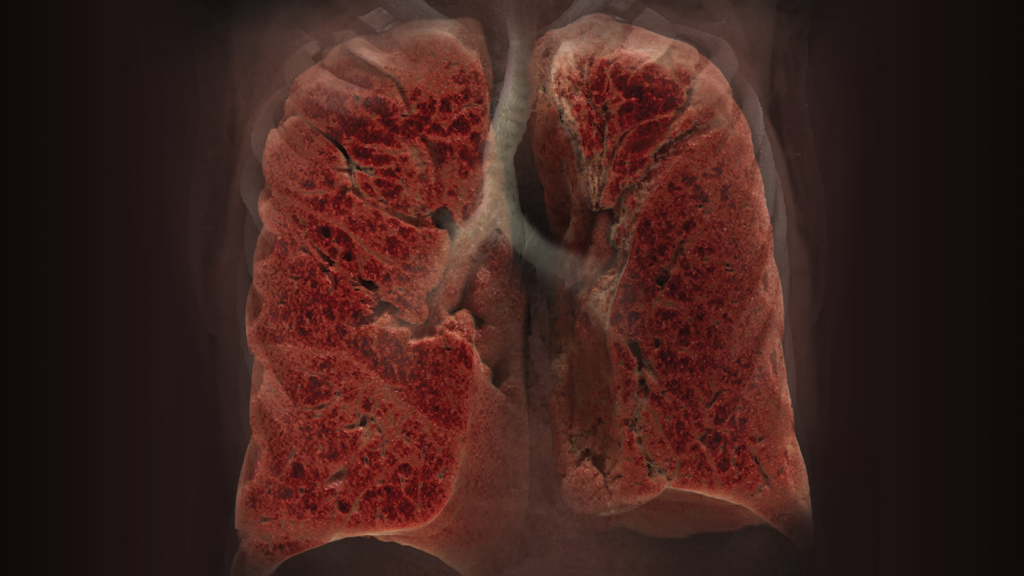

Global Illumination

Global Illumination is an alternate 3D rendering technique to help provide a more photorealistic view of human anatomy. Users are able to acquire and share these images for communication and education.